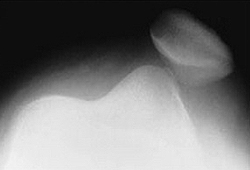

Вывихи надколенника — это нарушение соотношений между внутренней поверхностью надколенника и передней поверхностью большеберцовой кости. Вывих может быть боковым, вертикальным или торсионным. Независимо от вида вывиха повреждение сопровождается выраженным болевым синдромом, болезненностью и невозможностью движений в коленном суставе, пальпаторно определяемым смещением надколенника. Опора на ногу иногда частично сохранена. Диагноз выставляется по результатам осмотра и данным рентгенографии. Лечение заключается в вправлении надколенника и фиксации при помощи гипсовой повязки. В отдельных случаях показана операция.

Симптомы вывиха надколенника

Острый травматический вывих сопровождается резкой болью. Коленный сустав слегка согнут, увеличен в объеме, расширен в поперечном направлении (при боковых вывихах). Активные движения невозможны, пассивные болезненны и резко ограничены. Пальпаторно определяется направление и степень смещения надколенника. При полном вывихе надколенник располагается кнаружи от латерального мыщелка бедра, при неполном — находится над латеральным мыщелком.

Диагностика

Диагноз вывиха надколенника выставляется травматологом-ортопедом на основании характерного анамнеза, клинической картины и данных рентгенографии. Наиболее информативны сравнительные рентгенограммы обеих надколенников, проведенные при касательном направлении рентгеновских лучей спереди и сверху вниз или снизу вверх.